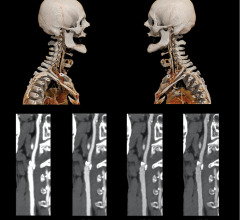

November 11, 2021 — A multidisciplinary team of scientists based at the Universidad de Valladolid and the Centro ...